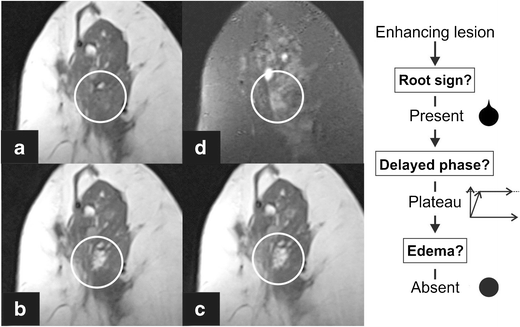

Apocrine ductal carcinoma in situ (DCIS) Grade 2 presenting as a mass lesion with the root sign, delayed plateau enhancement and perifocal oedema, resulting in a classification as Tree node 10. Representative axial slices of the T1-weighted, non-enhanced sequence (a), a T2 TIRM sequence (b), early (c) and delayed (d) post-contrast T1-weighted sequences are shown